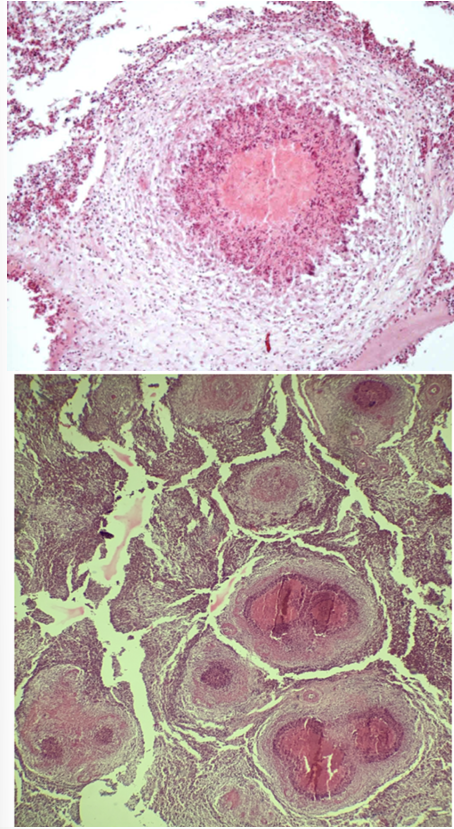

this is?

cholangitis et pericholangitis chronica hyperplastica (coccidiosis hepatis cuniculorum)

bile duct wall

papillary folds

coccidia

epithelial cells